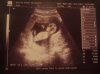

Haha no worries Sarah :) I'm really looking forward to this scan as the one at 7 weeks the baby was literally like a teeny blob but at this one we'll be able to make out a profile, feet, hands etc I just think its amazing the difference in 5 weeks lol x

Had my hospital visit today. Went really well, my dates are bang on so am 12w+3d today. Blood pressure is perfect but iron levels a little low so been given iron tablets to take each day. Had some blood taken, came out first time the woman was amazing! Usually they try both arms a few times then resort to a wrist or hand for the blood but not today......hope I get her again actually!

Got to see baby on the screen that was lovely. Very active, very long legs and a strong heartbeat :) He was moving around loads, his little feet kept wiggling and it looked like he was waving at us, it was so cute I was crying my eyes out. It really looked like he was flat on his back one arm behind the head, the other up and waving! Too early to tell the sex obviously but it looked like a boy!

I'm not sure if this will work or not, hopefully it does :)

• Baby xx.jpg